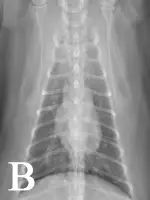

FIGURE 1

Bronchointerstitial pattern in the caudal lung fields (A and B). Enlargement of the caudal pulmonary arteries is evident on the ventrodorsal (B) projection.